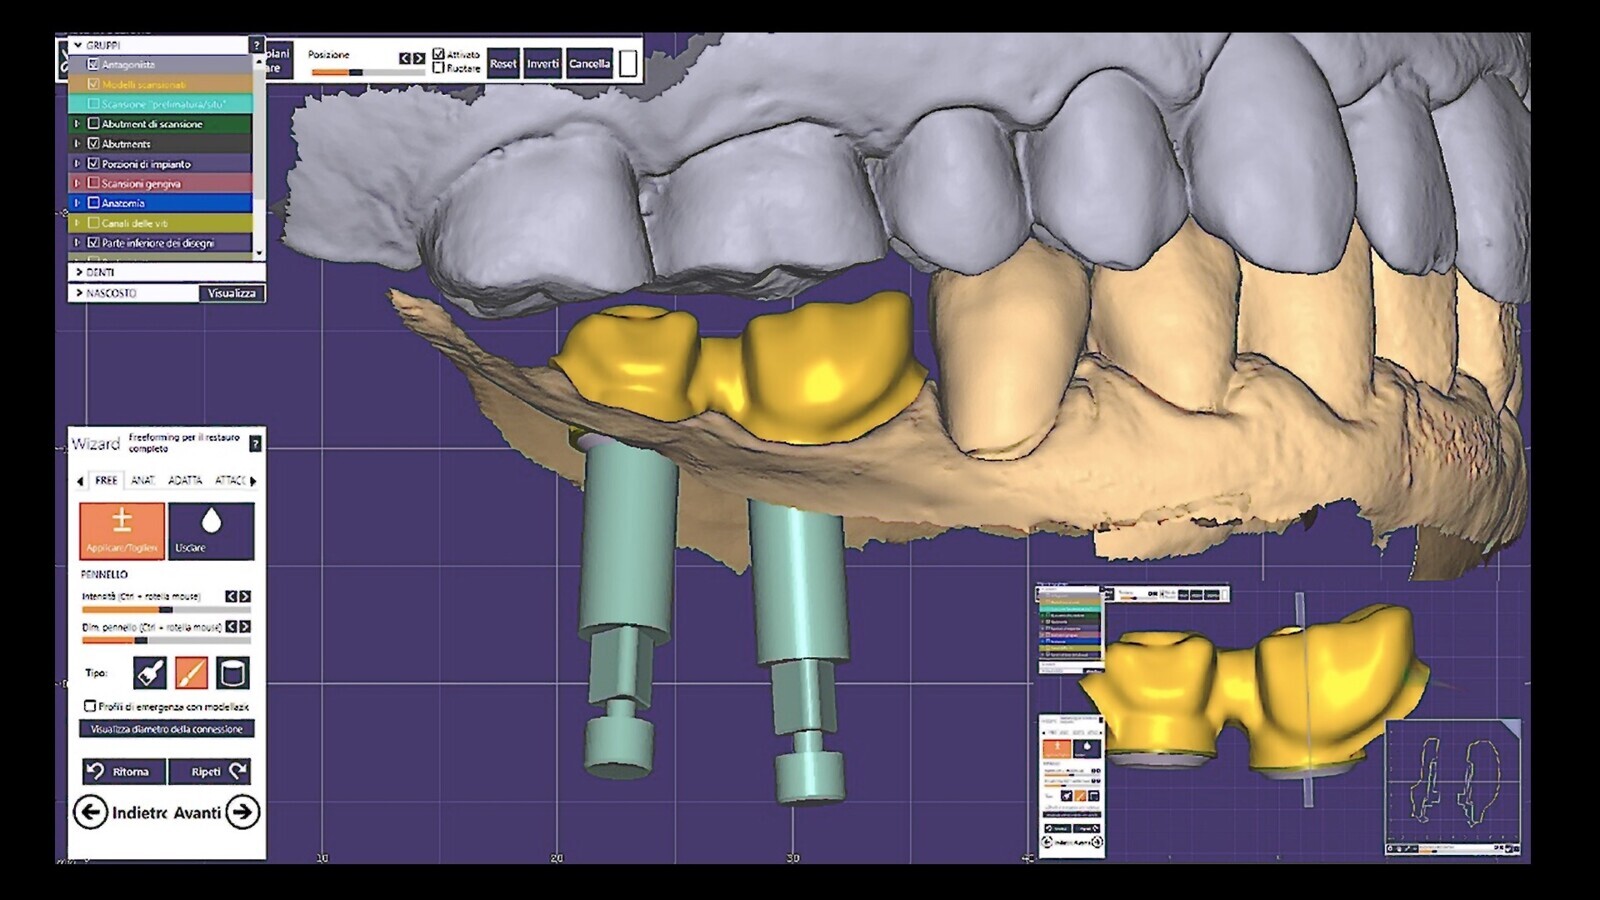

Figura 15. El escaneado permitió la confección del provisional mediante técnica digital.

Figura 16. Los provisionales fueron diseñados y fresados con la técnica CAD-CAM.

Figura 17. Posteriormente, fueron pegados a los pilares preformados extragrade (b).

Figura 20. Tres semanas más tarde, comenzamos el flujo de trabajo (en este caso completamente digital) para las coronas finales.

Figura 21. Para ello, se realizó una exploración intraoral del muñón natural y del Equator utilizando marcadores de exploración dedicados.